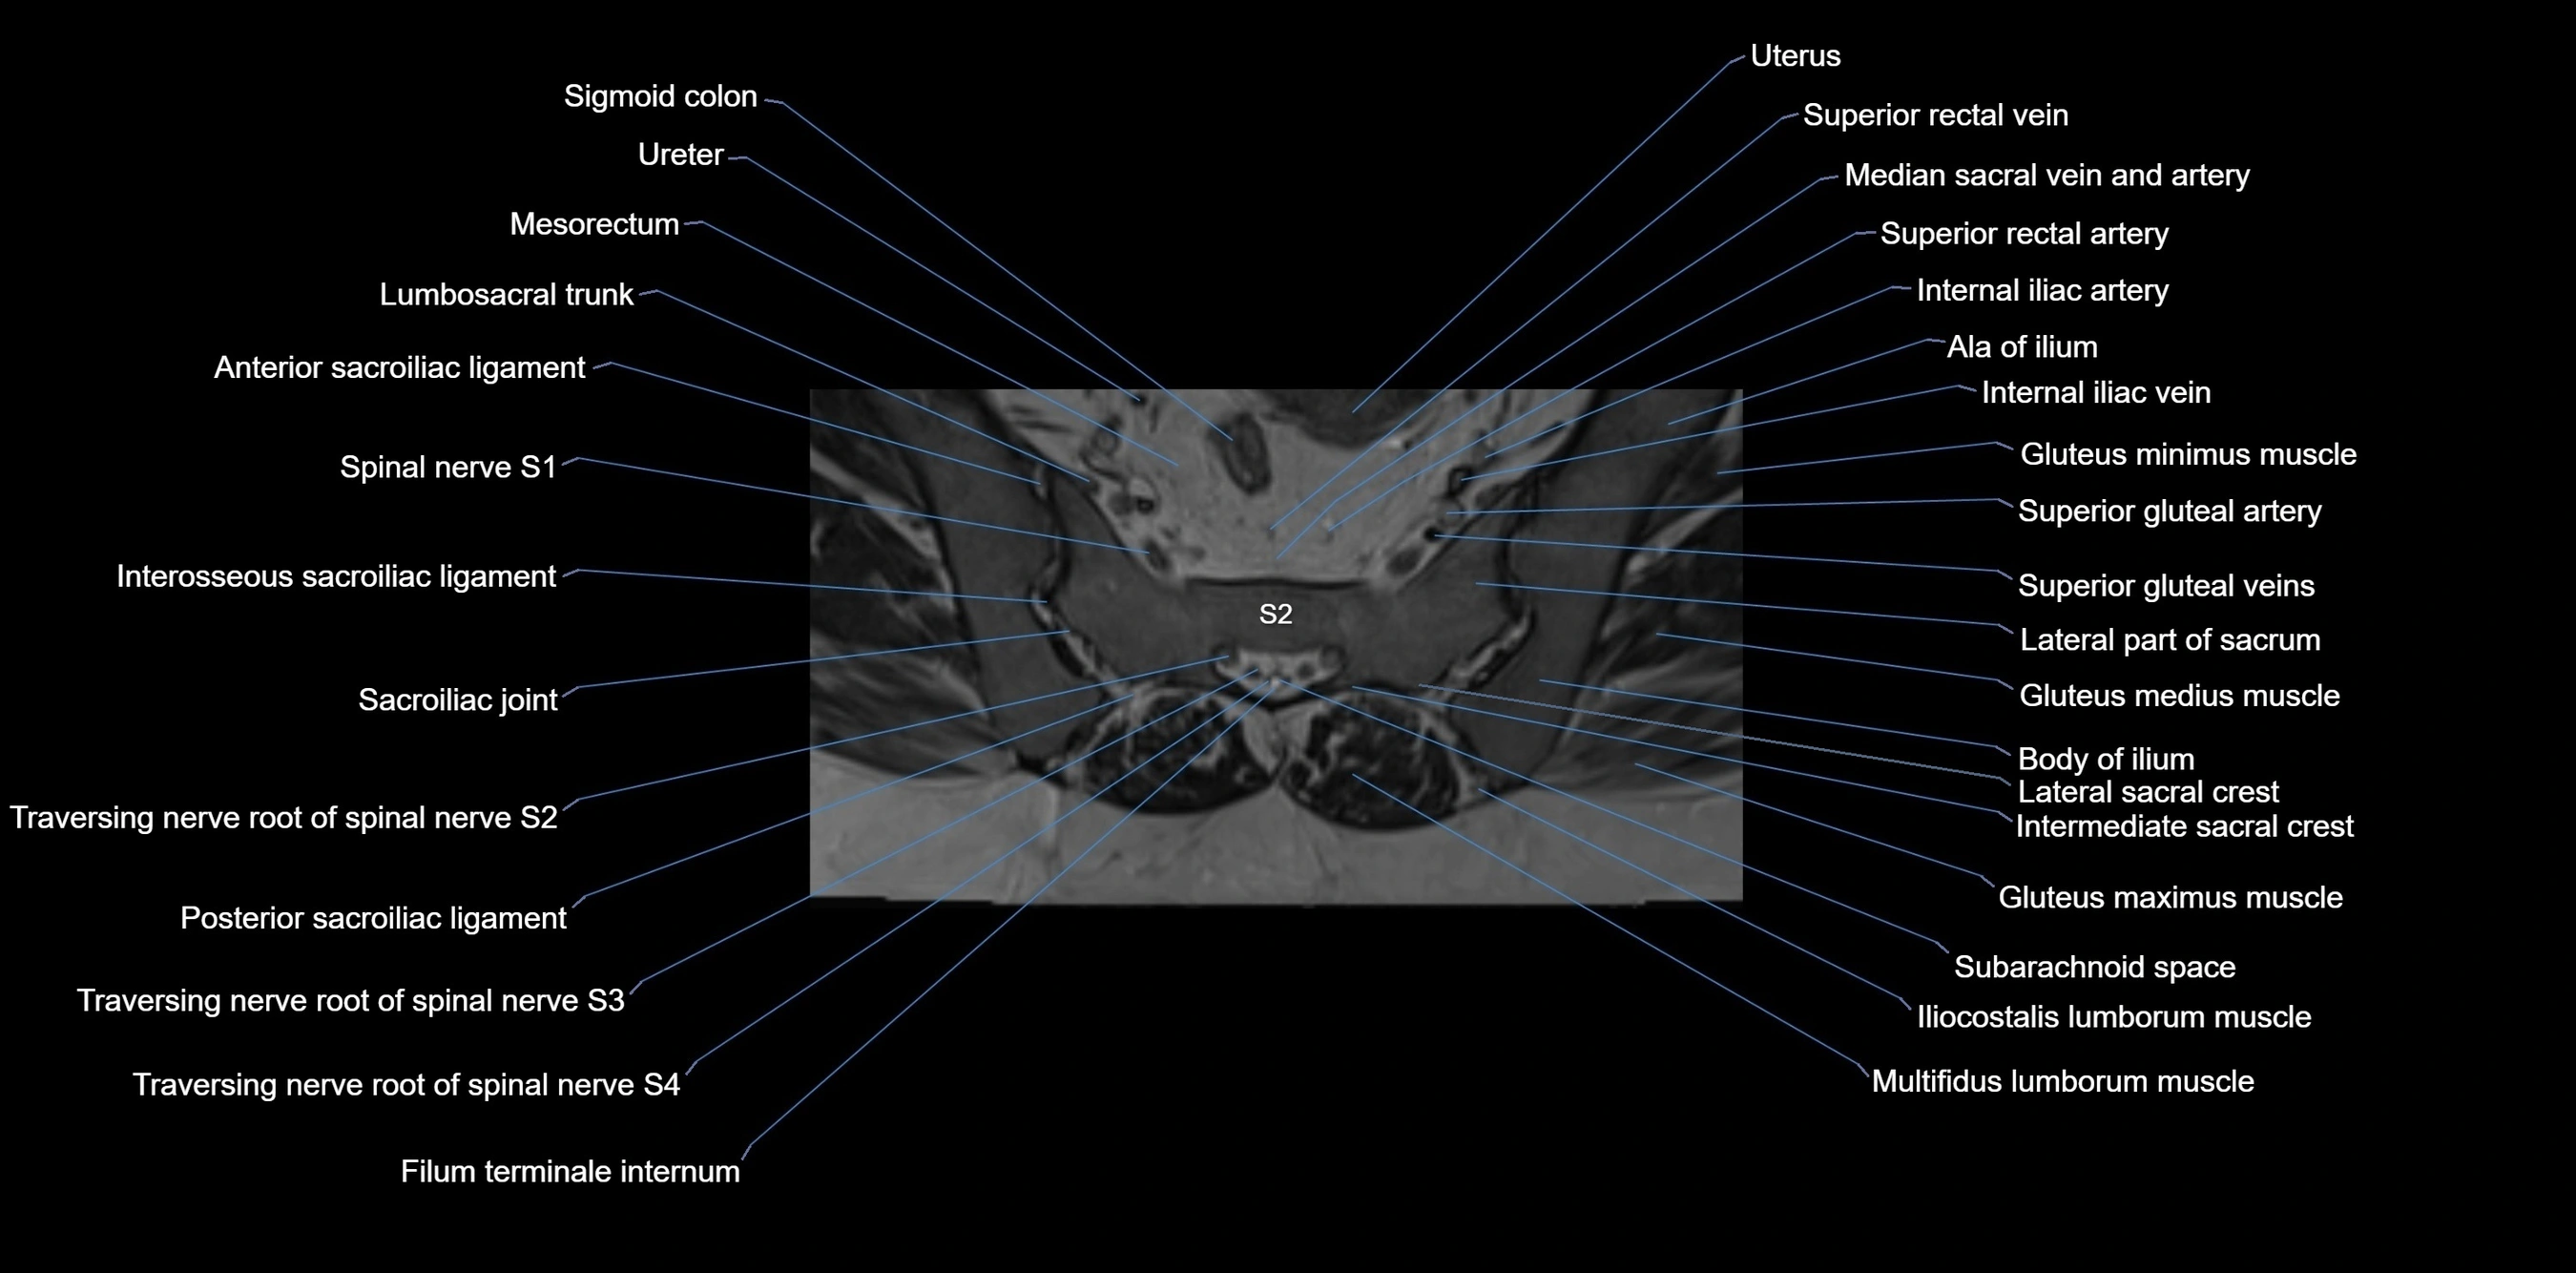

MRI image

image